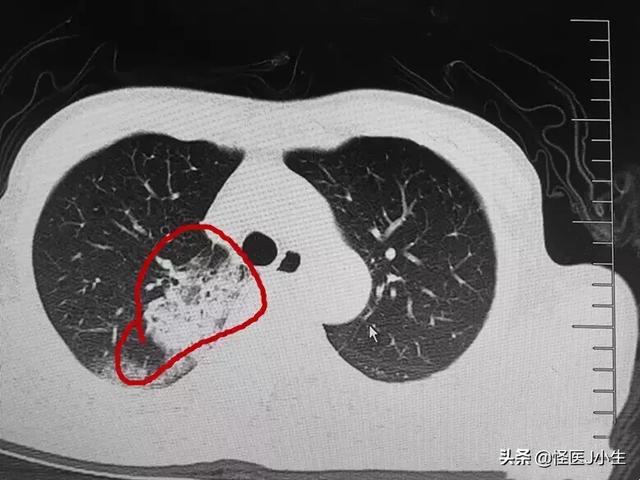

2.イメージング胸部レントゲン写真や肺のCT画像では、肺の外側の帯状に認められる斑状の影や、重症例では肺の固い影が認められることがある。

三、胸部CTは、発熱や咳などの顕著な症状を伴わないネオコロナウイルス肺炎への曝露歴を確認するために実施された。最終的にネオコロナウイルス肺炎と診断されるのは、両肺に複数の薄片状地中影が認められ、咽頭ぬぐい液の新型コロナウイルス核酸検査で陽性を示した場合である。